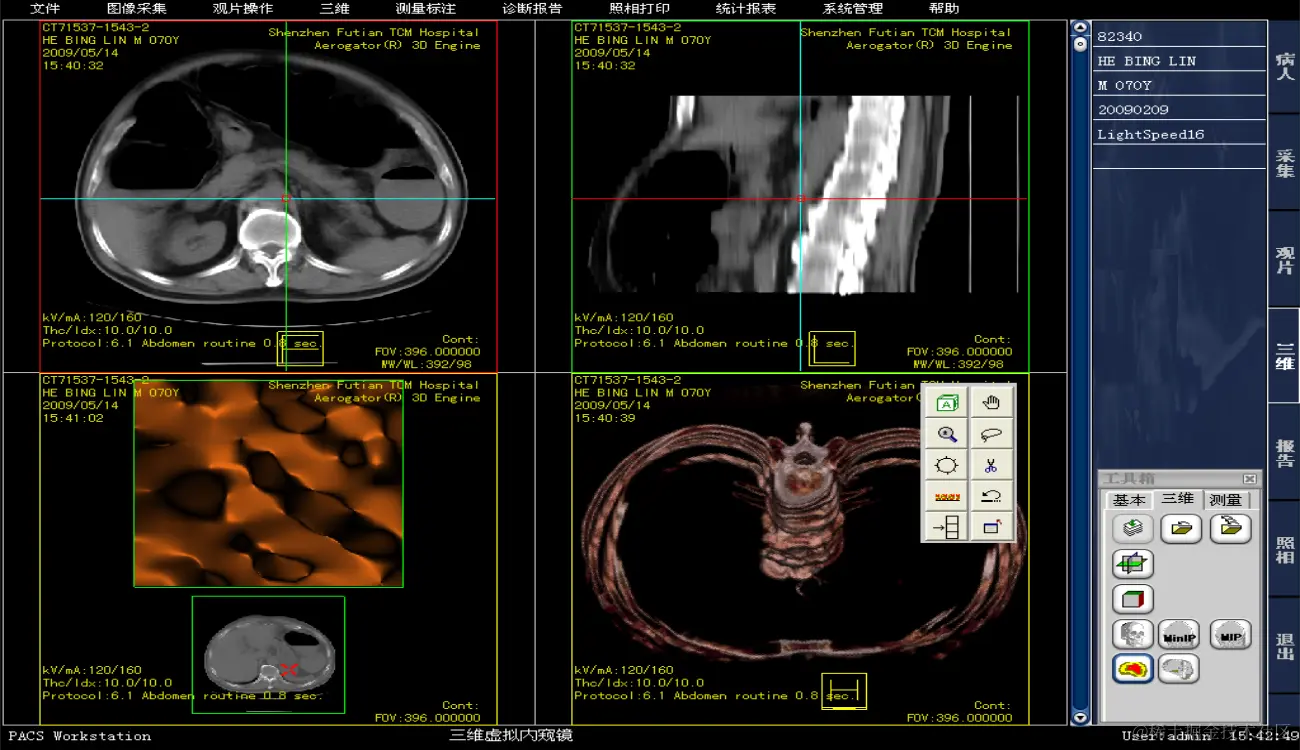

运维级医院PACS系统有源码,有演示,带使用手册和操作说明书 ,开发环境:VC + MSSQL

PACS系统可实现检查预约、病人信息登记、计算机阅片、电子报告书写、胶片打印、报表统计、数据备份等一系列满足影像科室日常工作的功能,并且由于影像数字化存储,用户可利用影像处理与测量技术辅助诊断、方便快捷地查找资料或利用网络将资料传输至临床科室,还可与医院HIS、LIS无缝连接。集成专业三维影像后处理功能,包括:三维多平面重建、三维容积重建、三维表面重建、三维虚拟内窥镜、最大/小密度投影、心脏动脉钙化分析等。